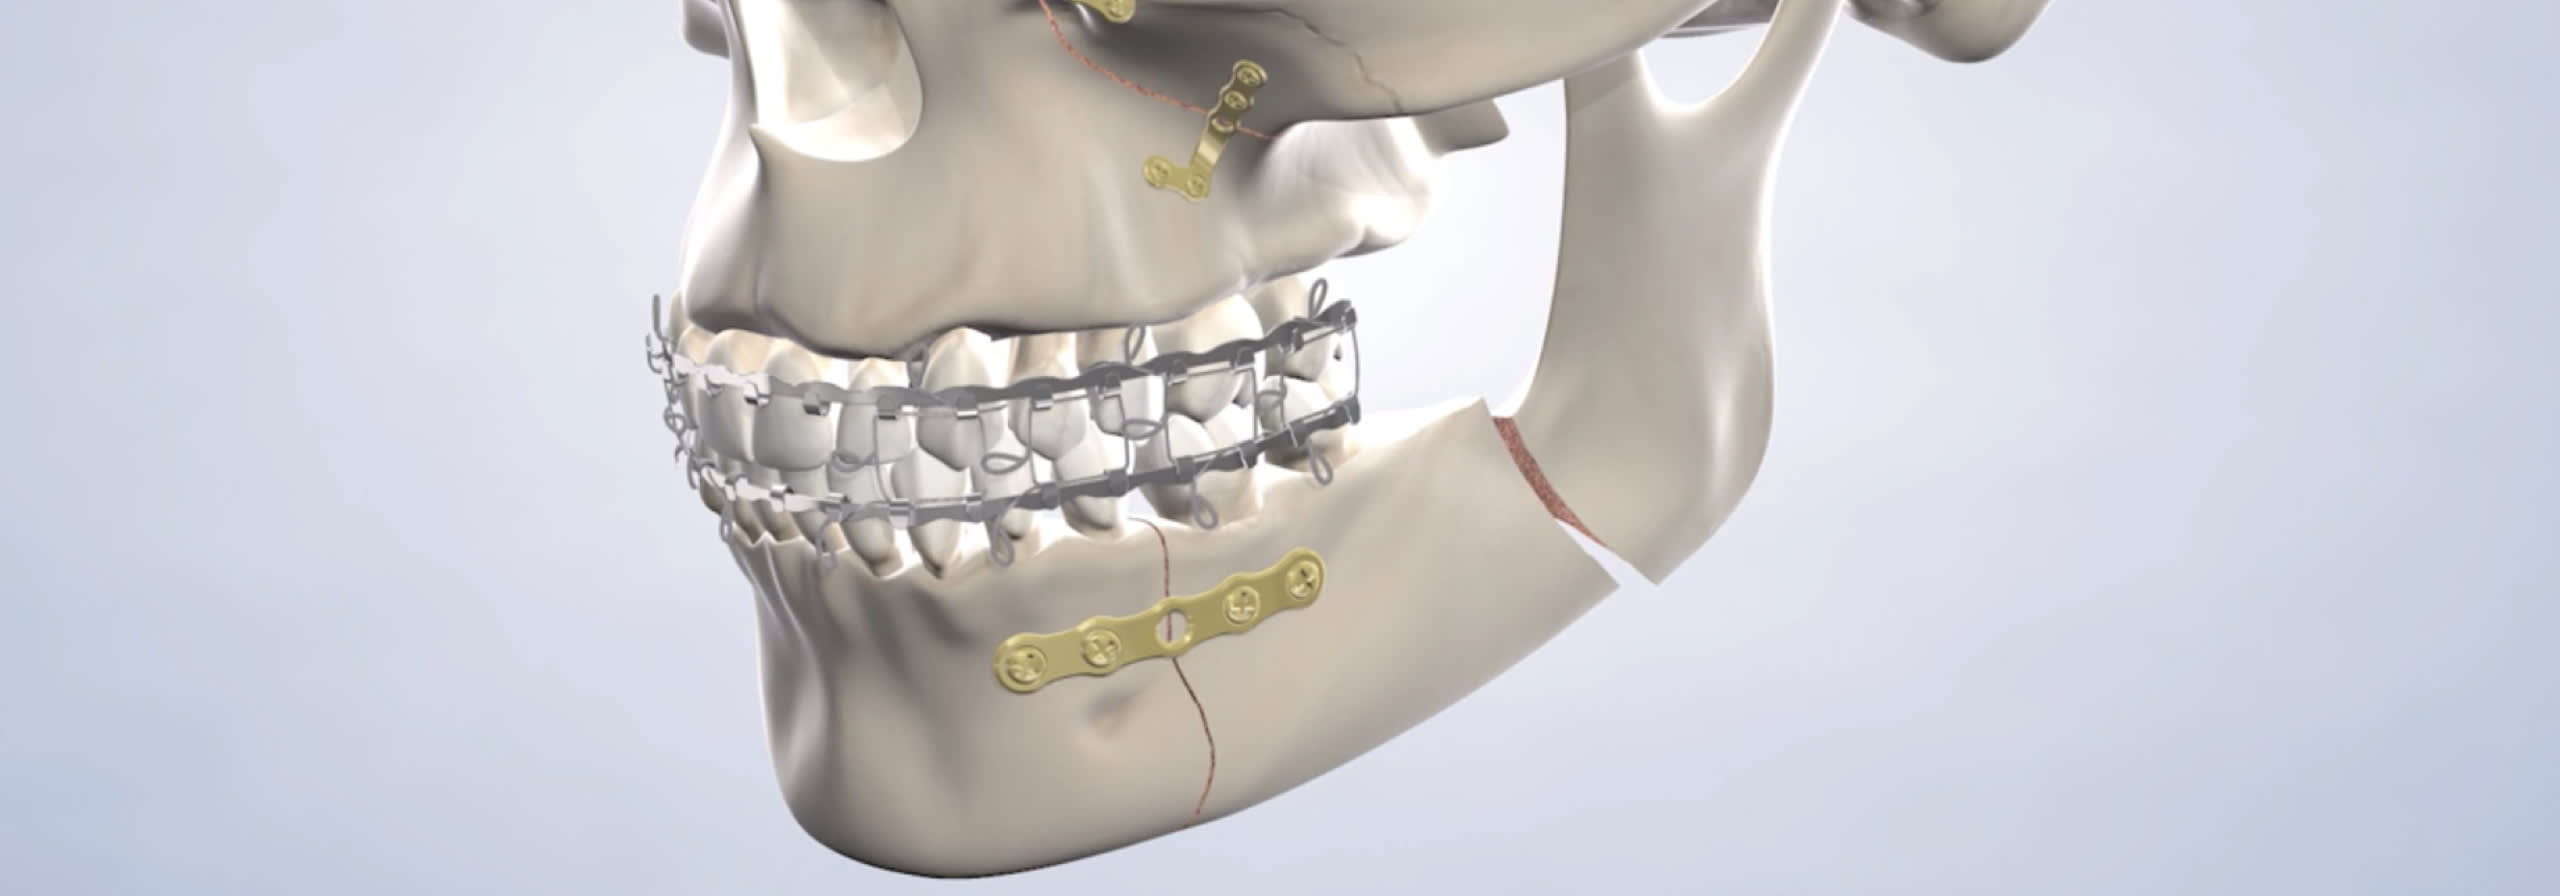

Soft tissue injuries may be treated with sutures, which are placed from within the mouth whenever possible or in less noticeable areas to reduce visible scarring. Bone injuries often require surgery, where your surgeon will use plates or screws to reposition and stabilize the face or jaw bones. Using screws and plates often eliminates the need to wire the jaws shut while they heal.